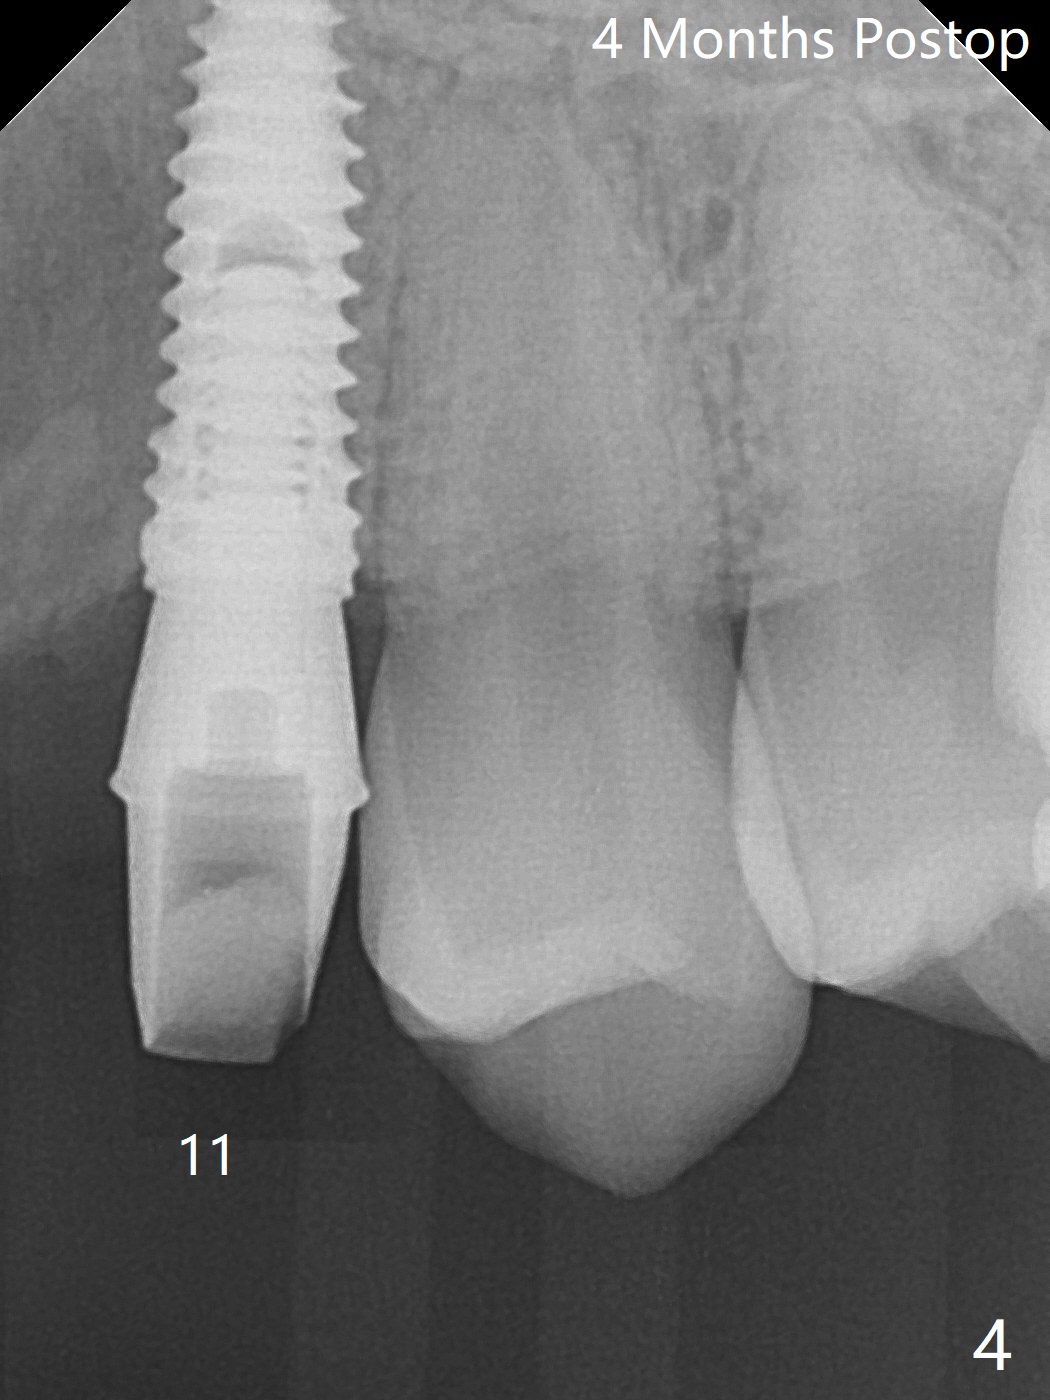

18岁男从外州大学回来,无症状,但是6号牙(右上尖牙)颊侧瘘道(图一,二(角化龈充分(箭头))),根尖片显示植体近中骨吸收(图三:*),而对侧植体仿佛骨整合(图四)。患侧切开后发现植体颊侧暴露,松动。拔除后骨缺损由粘性骨粉修复(图七,九:*),覆盖PRF膜(图七:P)和带钛网(图九:^)不可吸收膜(图五-七),后者用两个小钉子固定(图六(腭侧),七(颊侧),九),使用新的刀片和一个特殊尖头剥离器在颊侧骨膜下相当广泛分离,使用PTFE缝线,粘膜下水平褥式缝合之后(图八:箭头),多个垂直间断缝合,两个乳头垂直褥式缝合。术后一周伤口没有裂开,术后疼痛肿胀已经消退(图十)。术后十八天牙槽嵴仿佛比对侧还要宽(图十一,三与图十二,四(取模)对比)。术后5.5个月伤口没有裂开,牙槽骨,角化龈宽(图十六),与钛网和两个小钉子固定有关(图十五,十七)。CT显示牙槽骨只能容纳2.5或者3.0毫米植体(图十八)。11号牙植体牙冠粘固后没有骨质吸收(图十九),其实10,11号牙颊侧骨板隆起(图二十至二十二),而6植体失败,颊侧骨板吸收,甚至累及5号牙(图十七)。